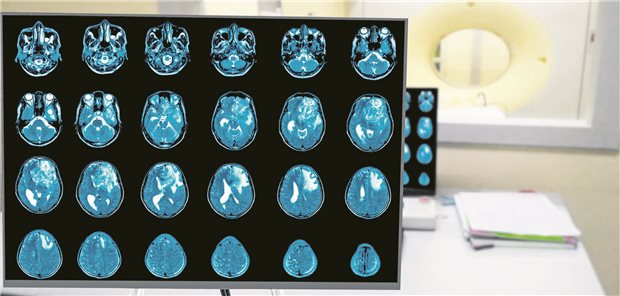

Themenseite ZNS-Tumoren/Hirntumor

Themenseite - ZNS-Tumoren/Hirntumor